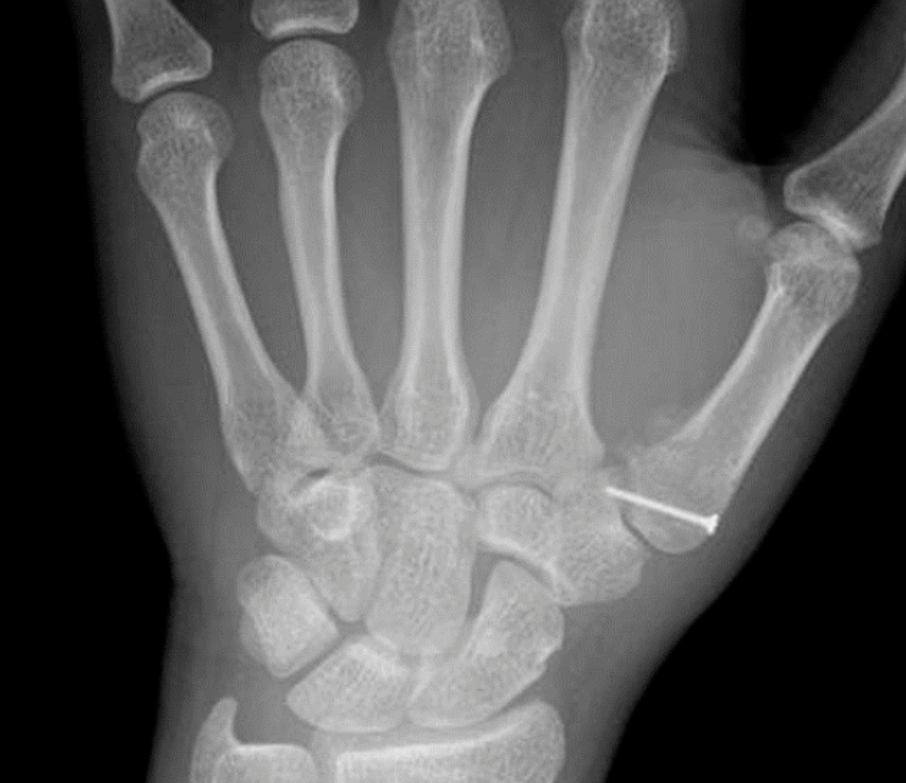

这些腕与手的骨折X线片如果没有标注箭头,你还能识别出来吗?